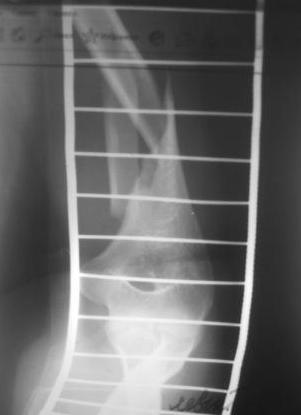

Перелом нестабильный, тактика - если позволяет сосояние больной, оперативное лечение. Как пример см. ниже, можно без скобы - стяжки с ЭПФ.

Представленный способ, функциональный, данная больная в качестве внешней иммобиллизации в течение 3-х недель полльзовалась косыночной повязкой, востановление функции плеча полное. Правда травма изолированная, но операция выполнялась через три недели после травмы, тот час после обращения ко мне - иногородняя.